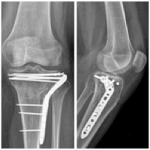

Abordaje anterolateral con osteotomía del epicóndilo en fracturas de platillo tibial. Resultados funcional y radiológico a los 6 meses de seguimiento

Víctor A. Ciccarello, Isaac Aranibar, Martín E. Romagnoli, Gonzalo J. Blanco O´Dena, David Espinoza Mendoza

Fracturas de platillo tibial tipo II-III de Schatzker tratadas con aloinjerto óseo impactado o técnica de rafting. ¿Es necesario llenar el vacío? Estudio de cohortes comparativo en 80 pacientes

Sebastián Pereira, Germán Garabano, Andrés Juri, Leonel Pérez Alamino, Joaquín Rodríguez, César Á. Pesciallo, Fernando Bidolegui